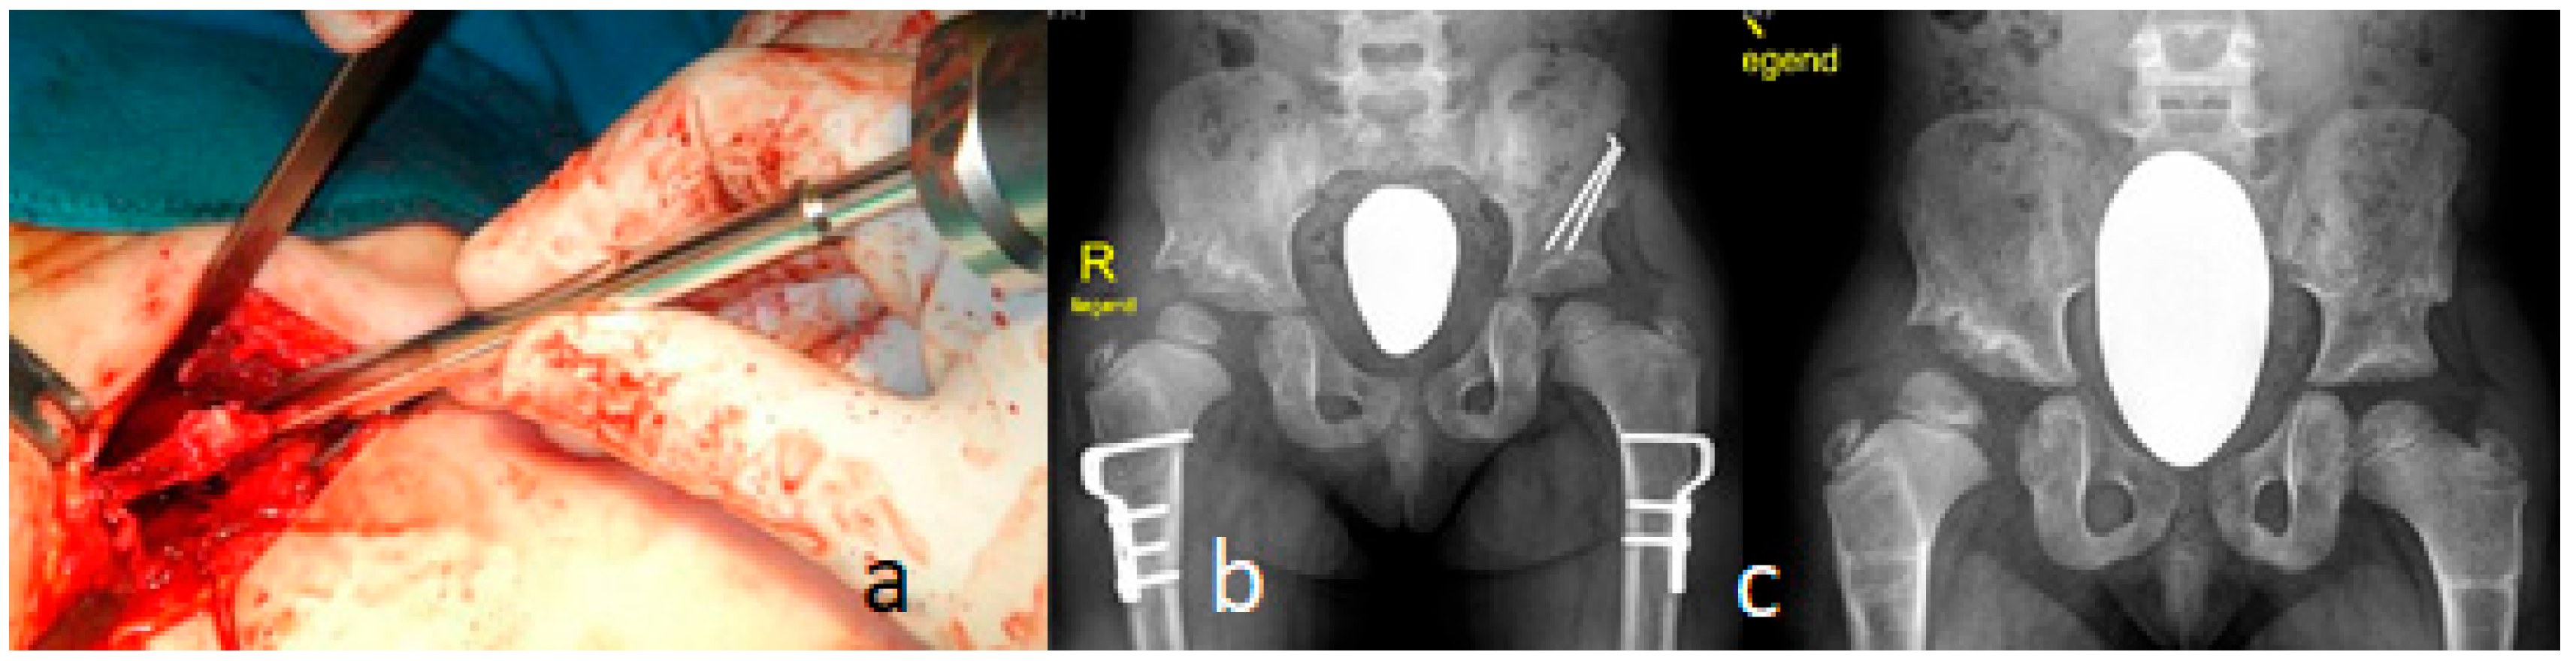

Congenital multiple dislocations often prove a difficult task for pediatric orthopedic surgeons. Skeletal deformities in Larsen syndrome can recur. The dislocated hip joints must be treated as early as possible. Since at the same time, there is often hyperlaxity of the knee joints with anterior dislocation of the tibia, conservative treatment with physiotherapy and a Pavlik harness must primarily be carried out. While it is usually possible to reduce the knee joints through slow repression, the hip joints have to be openly reduced, which is technically difficult because they are due to the Larsen syndrome’s extremely unstable joints. In order to achieve sufficient joint stability, the open reduction must be combined with a bony procedure in which the dysplastic acetabulum is corrected. The surgical method according to Pemberton/Dega has proven successful in our hands, in which a slightly curved chisel is inserted in the cranial area to the edge of the acetabulum, the ileum is severed to just above the Y joint, and a triangular bone graft inserted into the osteotomy gap is fixed with a K wire. Depending on the existing anatomical conditions, an intertrochanteric osteotomy may also be indicated—for example, in the case of increased ante torsion of the femoral neck—in order to achieve optimal centering and stability of the femoral head in the joint socket. Because of the bony procedures, the surgery is not indicated before the age of 12 months. We performed it simultaneously combined proximal femoral varus osteotomy, and shelf acetabuloplasty has been performed in a 14-month-old girl with Larsen syndrome. The aim of these surgical procedures is to assure good containment of the bilateral hip dislocation. A double incision was used for this type of surgery (Figure 6a). Proximal femoral osteotomy for varization and de-rotation was performed at the intertrochanteric level (Figure 6b). In the postoperative period, neck-shaft angles were never reduced to less than 110°, and the de-rotation angle was less than 20° (Figure 6c).

Figure 6.

(a–c): A double incision was used for this type of surgery in a 14-month-old girl with Larsen syndrome (a). Proximal femoral osteotomy for varization osteotomy and de-rotation was performed at the intertrochanteric level (b). In the postoperative period, neck-shaft angles were never reduced to less than 110°, and the de-rotation angle was less than 20° (c).